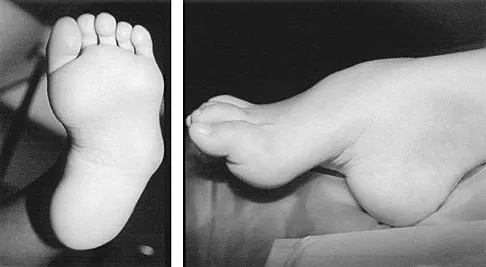

A senior resident is scheduled to perform a posterior medial release on a 10-month-old infant who has a congenital clubfoot deformity. Informed consent is obtained for the procedure. The supervising surgeon is obligated to give the parents what information?